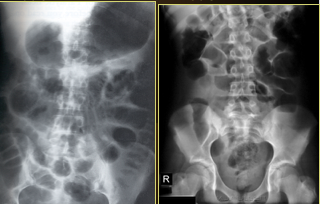

Which one is small v. latge bowel obstruction?

top: small bowel w/valvulae conniventes

bottom: large bowel w/haustrations

What type of bowel gas pattern?

Large Bowel Obstruction

What does this show?

complete colonic obstrucion

obstructing carcinoma in descending left colon = proximal air-fluid levels

absence of air distally in the rectum or sigmoid = complete obstruction

ileocecal valve is competent so there is no small bowel air